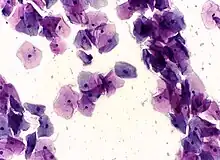

Normal cervical cells in a Pap smear

In the conventional Pap smear, the collected cells are smeared on a microscope slide, and a fixative is applied. The slide is evaluated in a pathology lab to identify cellular abnormalities.